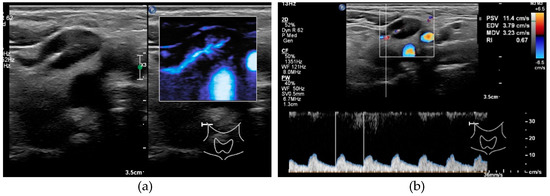

Figure 3.

Ultrasound features of a benign node. (a) Hilum sign in a benign node, no peripheral vascularity. (b) Measurement RI 0.67.